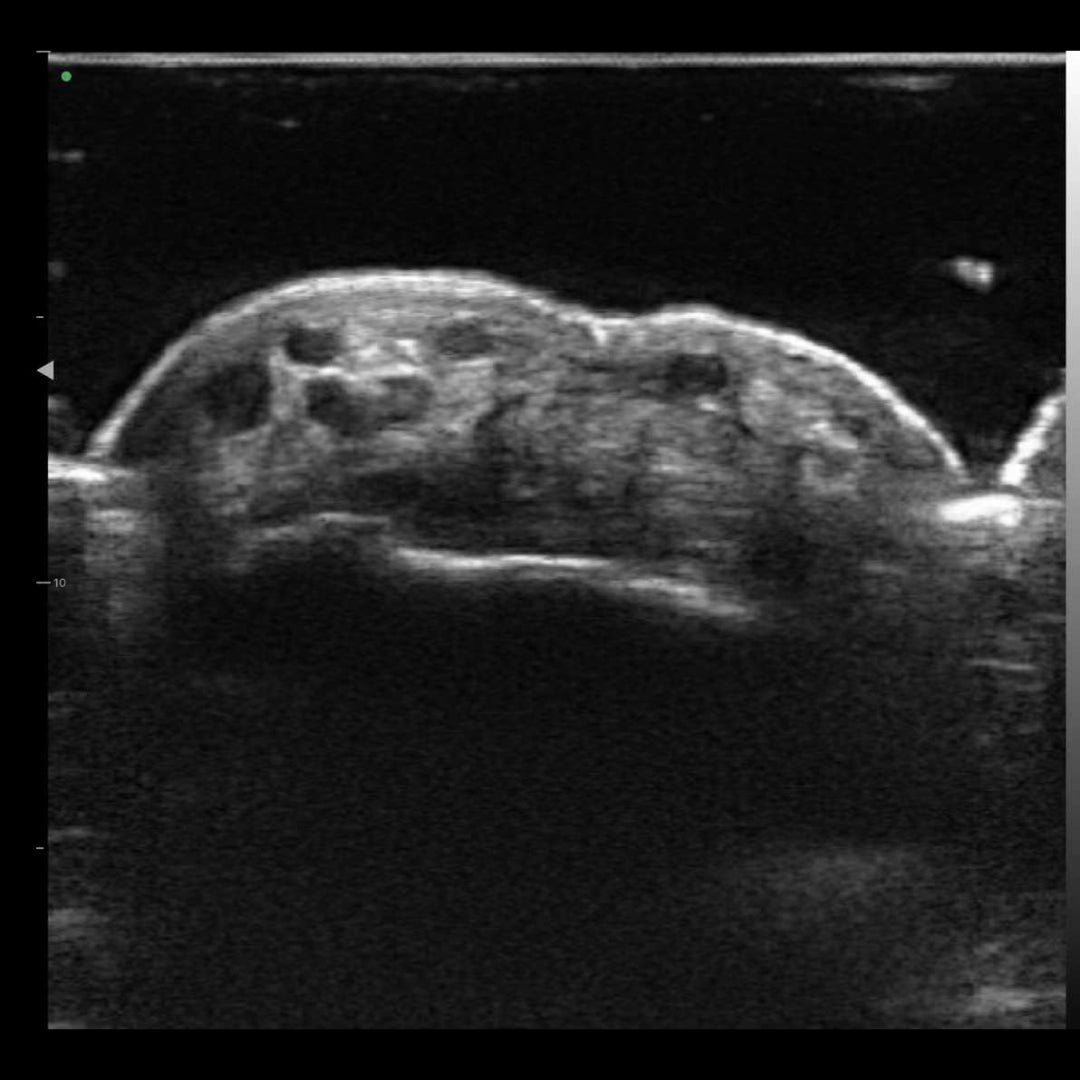

Imágenes de la vida real

Nuestros dispositivos reproducen una excelente calidad de imagen.